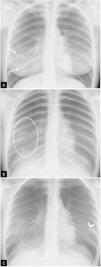

Pueden ser causa de falsos positivos en las radiografías de tórax la falta de inspiración, la prominencia mamaria y el mal posicionamiento del paciente, que puede condicionar que las escápulas y las partes blandas se proyecten sobre los campos pulmonares aumentando la densidad de la periferia del pulmón y simular opacidades en vidrio deslustrado (fig. 1). La sensibilidad de la radiografía de tórax portátil en la detección de pacientes con COVID-19 respecto a la PCR ha sido objeto de numerosos estudios que inicialmente no demostraron valores muy altos24, aunque ha mejorado hasta el 89% en entornos con una prevalencia muy alta de la enfermedad29.

Falsos positivos o pitfalls. A y B) Radiografía de tórax poco inspirada. Mujer de 38 años con clínica sospechosa de enfermedad COVID-19. A) Radiografía de tórax posteroanterior. Aumento de la densidad bilateral, de predominio en campos medios e inferiores, sospechoso de neumonía por COVID-19 (puntas de flecha). Escasa inspiración (se identifican 7 arcos costales posteriores) y mamas voluminosas. B) Misma paciente. Repetición de radiografía de tórax a los pocos minutos tras inspiración forzada, donde se objetiva desaparición de todos los hallazgos descritos previamente (obsérvese el cambio en la morfología de la silueta cardíaca). C) Artefacto por aumento de densidad mamaria. Mujer de 18 años con clínica sospechosa de enfermedad COVID-19. Opacidades bilaterales y simétricas en campos inferiores producidas por la alta densidad del tejido mamario (flechas). PCR negativa para SARS-CoV-2.

Hallazgos típicos o aquellos que se han asociado comúnmente en la literatura científica a COVID-19 (fig. 2). Incluyen el patrón reticular, las opacidades en vidrio deslustrado y las consolidaciones, con morfología redondeada y una distribución multifocal parcheada o confluente. La distribución suele ser bilateral y periférica y predominantemente en los campos inferiores23 (fig. 2). El diagnóstico diferencial incluye la neumonía organizada, la toxicidad farmacológica y otras causas de daño pulmonar agudo. Entre la primera y la tercera semana desde el inicio de los síntomas, los hallazgos radiológicos típicos pueden evolucionar hacia una enfermedad difusa. Esto se relaciona con una situación clínica grave de hipoxemia y el principal diagnóstico diferencial es el síndrome de distrés respiratorio agudo (SDRA).

Figura 2.Hallazgos típicos de la neumonía COVID-19. A) Mujer de 47 años con sospecha clínica de enfermedad COVID-19. Radiografía de tórax posteroanterior (PA). Patrón intersticial-reticular de predominio periférico (flechas). B) Misma paciente que en imagen A. Radiografía de tórax PA realizada 3 días después. PCR positiva para SARS-CoV-2. Aunque la radiografía está menos inspirada, se objetiva la aparición de tenues opacidades alveolares (flechas punteadas) redondeadas bilaterales y periféricas. C) Varón de 57 años con disnea y PCR positiva para SARS-CoV-2. Opacidades periféricas bilaterales en campos superiores, medios e inferiores (puntas de flecha). D) Varón de 45 años con disnea y COVID-19 confirmada con PCR. Radiografía de tórax anteroposterior con múltiples áreas de consolidación confluentes difusas bilaterales que afectan extensamente a ambos pulmones. Nótese la presencia de dos vías venosas centrales, una yugular izquierda y otra subclavia derecha (flechas blancas) y de sonda digestiva (flecha negra).

Hallazgos indeterminados o aquellos que pudiendo presentarse en casos de neumonía COVID-19 pueden tener otras causas. Incluyen las consolidaciones o las opacidades en vidrio deslustrado con distribución unilateral, central o en los lóbulos superiores (fig. 3A). El diagnóstico diferencial incluye otras infecciones y el edema alveolar.

Figura 3.Hallazgos atípicos de neumonía COVID-19. A) Neumonía lobar. Varón de 28 años con clínica compatible con enfermedad COVID-19 y PCR positiva para SARS-CoV-2. Radiografía de tórax en proyección posteroanterior (PA). Afectación del lóbulo superior derecho (flecha). B y C) Afectación bilateral y derrame pleural. Varón de 17 años con fiebre y PCR positiva para SARS-CoV-2. Radiografía de tórax PA (B) y lateral (C). Tenues infiltrados bilaterales en campos inferiores (flechas) con mínimo derrame pleural en el seno costodiafragmático posterior izquierdo (punta de flecha).

- •

Hallazgos atípicos o aquellos poco frecuentes o no descritos en neumonía COVID-19. Incluyen la consolidación lobar, el nódulo o la masa pulmonar, el patrón miliar, la cavitación y el derrame pleural, descrito solo en el 3% de los pacientes23 y más típico de la enfermedad avanzada (fig. 3B y C).